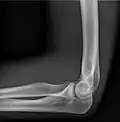

• Elbow - AP and Lateral. Radial head projections available on request

• Soft tissues are seen with the same machine as for hard tissues, but a "softer" or less-penetrating X-ray beam is used. Tissues commonly imaged include the lungs and heart shadow in a chest X-ray, the air pattern of the bowel in abdominal X-rays, the soft tissues of the neck, the orbits by a skull X-ray before an MRI to check for radiopaque foreign bodies (especially metal), and of course the soft tissue shadows in X-rays of bony injuries are looked at by the radiologist for signs of hidden trauma (for example, the famous "fat pad" sign on a fractured elbow).